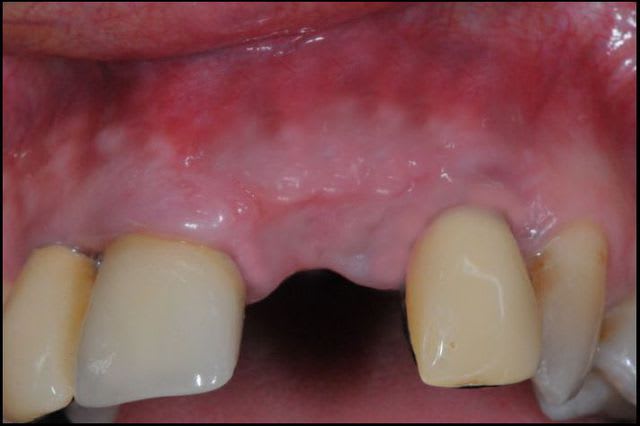

Le cas EII sur 12

positionnement de l'implant en ménageant un espace en vestibulaire qui st comblé avec de l'os synthétique car l'espace est important et il y a une perforation de la corticale vestibulaire en regard de l'apex de la dent.

pour recouvrir tout cela et gagner un peu de volume vestibulaire

un lambeau palatin pédiculé qui après une rotation va recouvrir l'implant et la greffe.